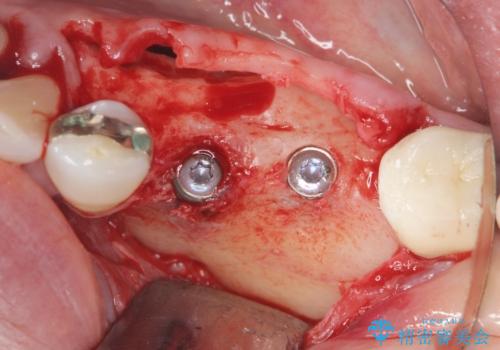

舌側にある大きな骨隆起を除去するとともに、除去した骨と人工骨を用いてインプラント周囲の骨を造成します。

自家骨と人工骨による骨造成は、長期的に見て安定し吸収が少ないとされる骨の造成法です。

インプラント周囲に、必要十分な骨を作ることが長期渡りインプラントにトラブルを起こしにくい鍵となります。